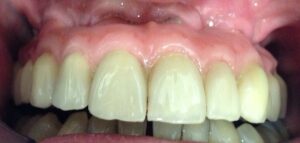

Sette giorni dopo l’inserimento delle viti di guarigione fig.10 si passa all’inserimento dei provvisori che resteranno fissi per circa 2 mesi fig.11-12. Questi provvisori facilitano la programmazione per la realizzazione dei definitivi e guidano la crescita della gengiva fig.13 in modo corretto intorno ai denti per avere un effetto estetico migliore.

Successivamente si preparano i monconi fresati con strutture in lega aurea fig.14-15, si passa alla ceramizzazione delle strutture, quindi rifinitura, lucidatura e inserimento in bocca delle corone ormai pronte e definitive fig.17-18-19.